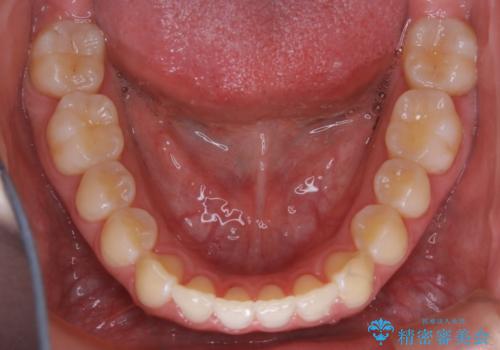

初診時の写真では一見噛み合わせには問題がないように見えても、実際に精密な検査を行うと改善すべき点が見つかる場合も多くあります。

当院では、矯正治療は見た目の改善が主目的ではなく機能面を改善し自然に長持ちする口腔内環境を整えることに重きを置く必要があると考えます。

しかしながら、こちらの理想だけを押し付けるだけが良い治療とは言えないので、患者様と治療のゴールの設定をよく話し合ったうえで方針を決定していくことが最も重要です。